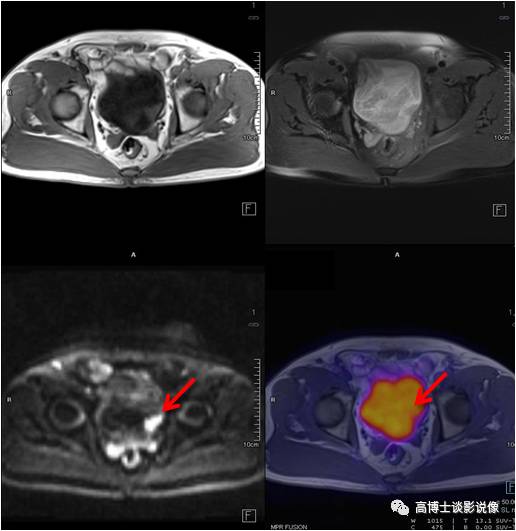

前列腺癌

老年男性,腹痛一周伴低热。PET/MR示前列腺左后方外周带见类圆形异常信号灶,直径约1.1cm,FDG摄取稍增高。之后穿刺证实为前列腺癌。

点评

前列腺癌高峰年龄是70~80岁,早期常无症状,血化验PSA升高,可以帮助筛查,但是有相当一部分前列腺炎症PSA也会升高,所以进一步鉴别需要依靠MRI/ PET,查出病变后还可以指导临床选择穿刺部位。

宫颈癌

中年女性,下腹部坠胀感1月。宫颈可见一类圆形软组织信号,大小约2.3cm× 2.5cm ,FDG摄取增高,病理诊断为宫颈鳞状细胞癌。

宫颈癌是最常见的妇科恶性肿瘤。高危型HPV持续感染是宫颈癌的主要危险因素。宫颈刮片细胞学检查是主要的筛查方法。PET对宫颈浸润癌的诊断准确性较高,对于术前分期和治疗后疗效评估很有价值。